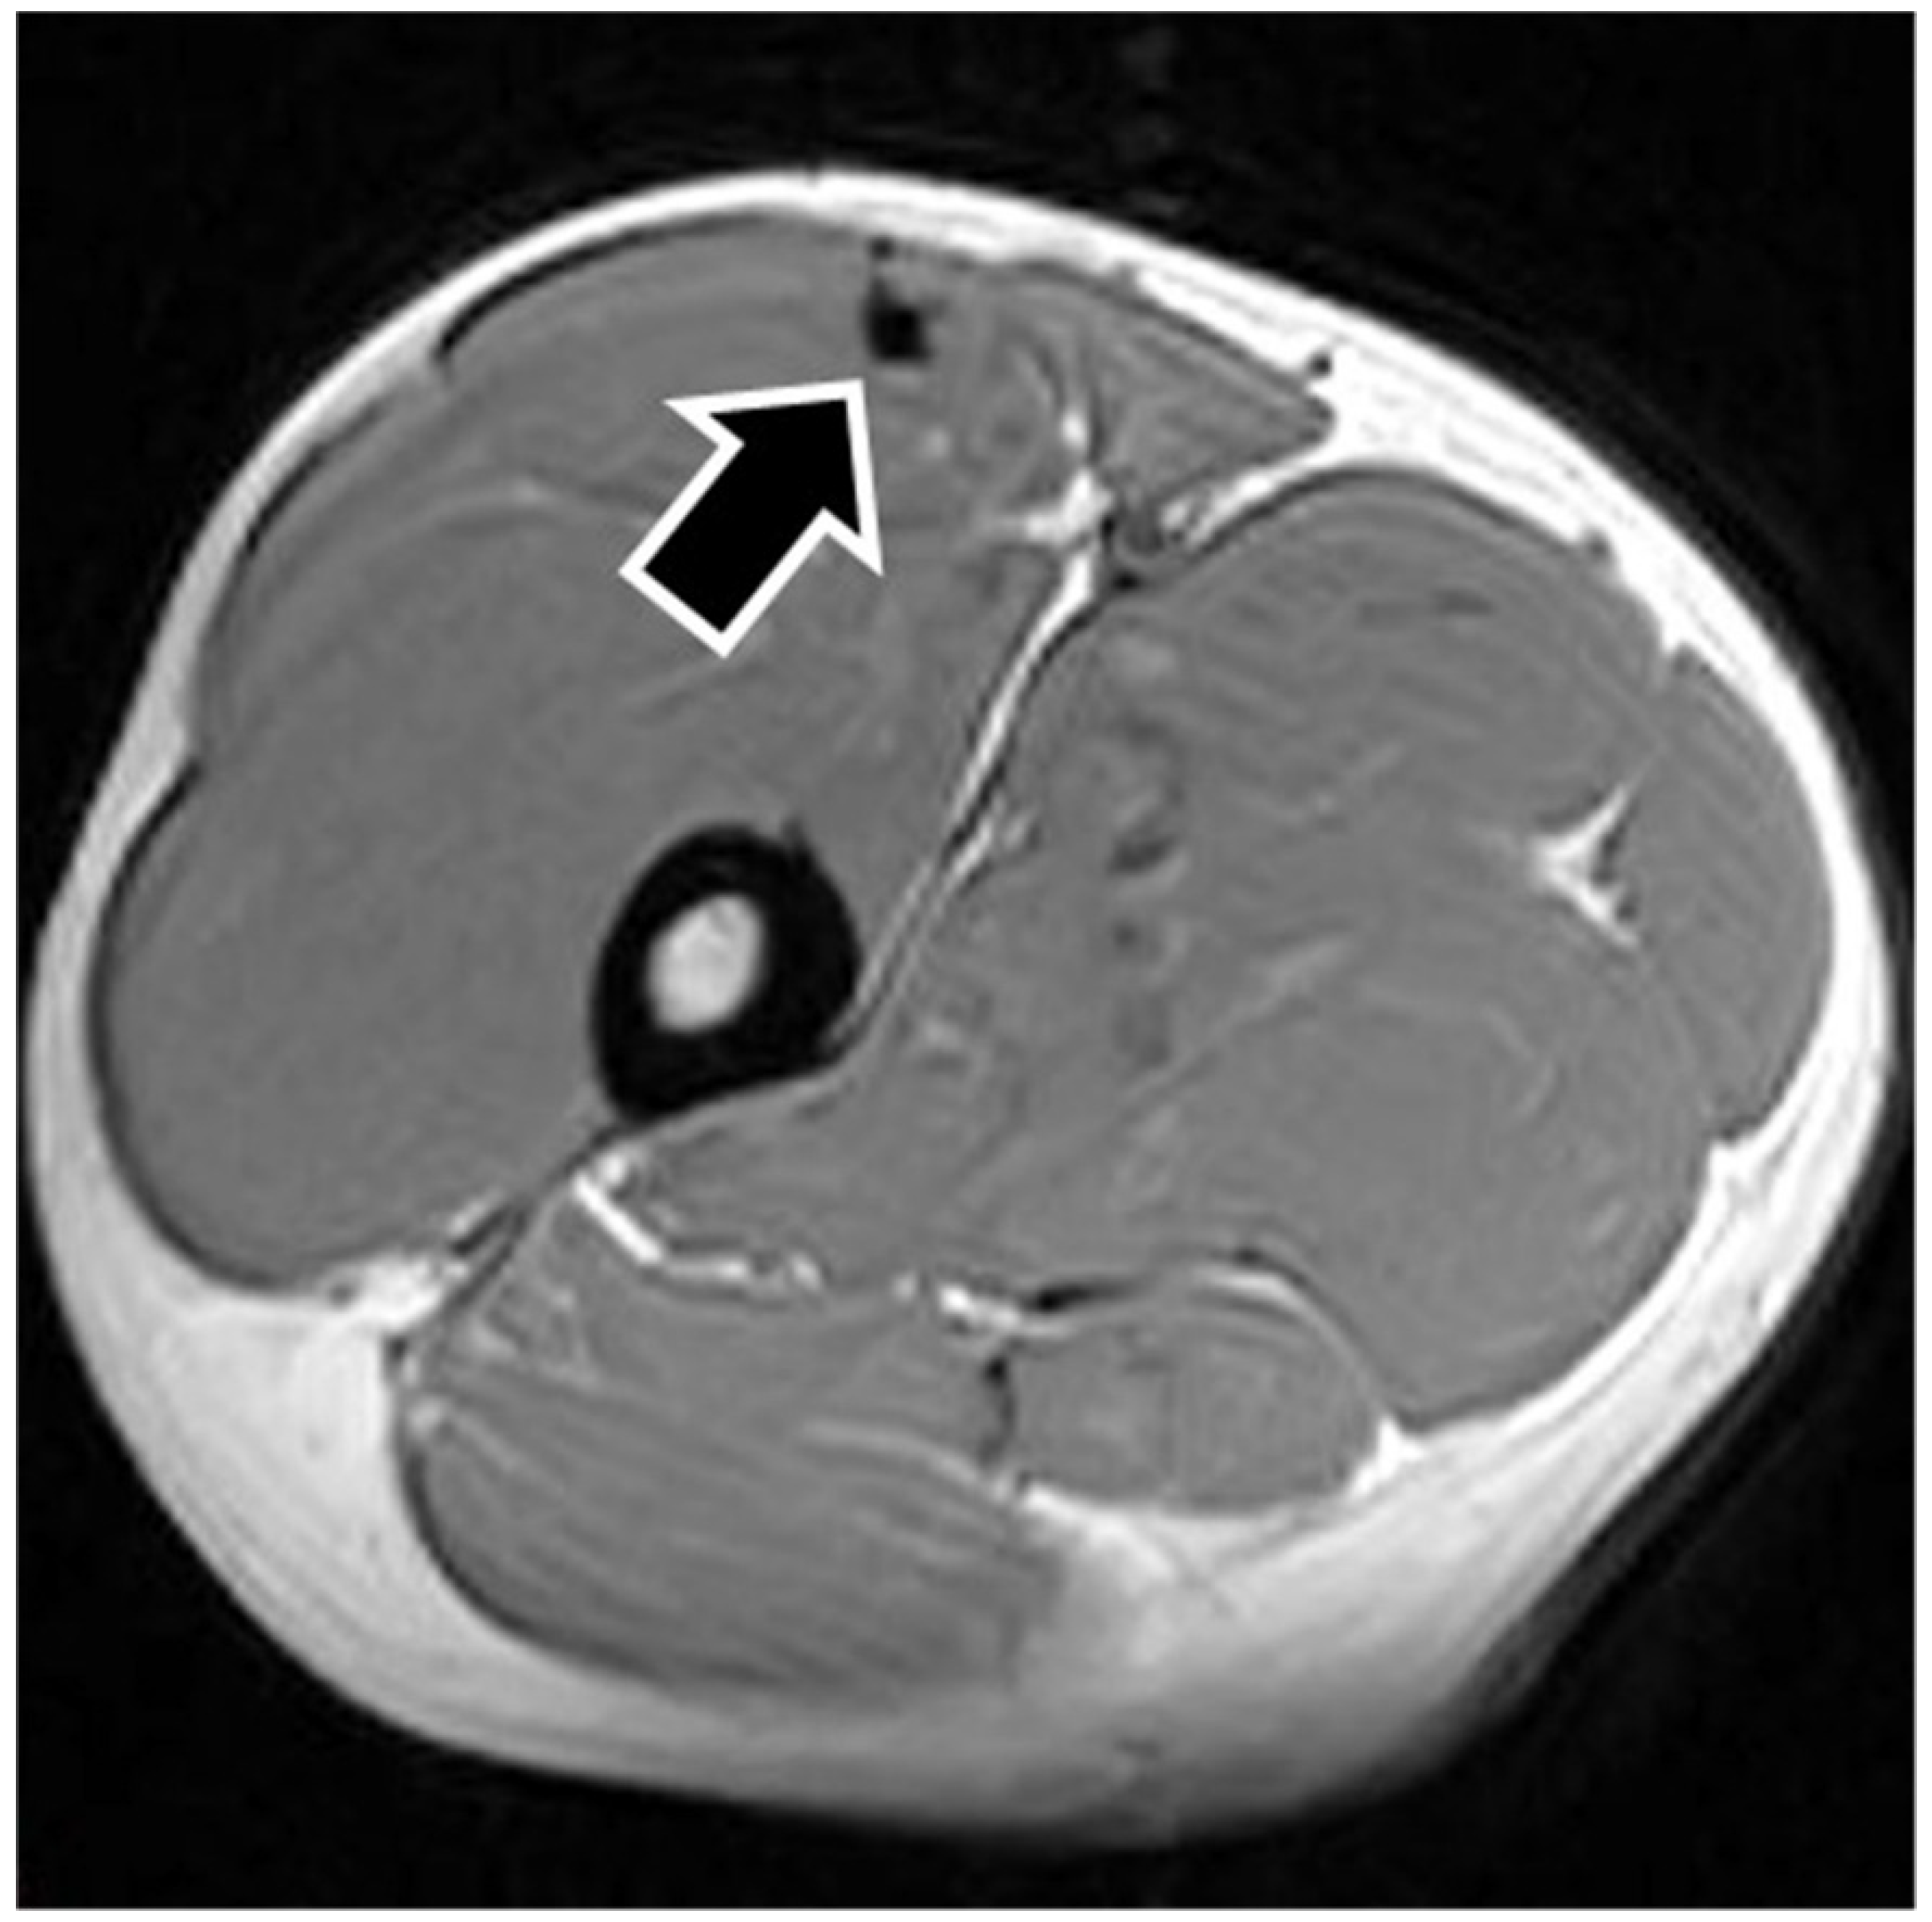

MRI findings are shown in Table 1. In eight of the RF strain injuries, a low signal area was noted in the central tendon (Figure 2). In four of the RF strain injuries, a low signal area was noted in the myofascial junction of the RF (Figure 3). In four of the RF strain injuries, the axial T1-weighted image did not show a low signal (Figure 4). The longitudinal range of the injured region in the 12 RF that showed a low signal area in MRI was approximately 8.8 cm (range, 4–17 cm). When the injured part was limited to the central tendon, the longitudinal range of the injured region was approximately 10.5 cm (range, 5–17 cm).

Figure 3. Injured rectus femoris muscle with a history of affecting the myofascial junction. The figure shows an example of myofascial junction injury. The axial T1-weighted image shows a low signal in the myofascial junction of the rectus femoris muscle (black arrow).